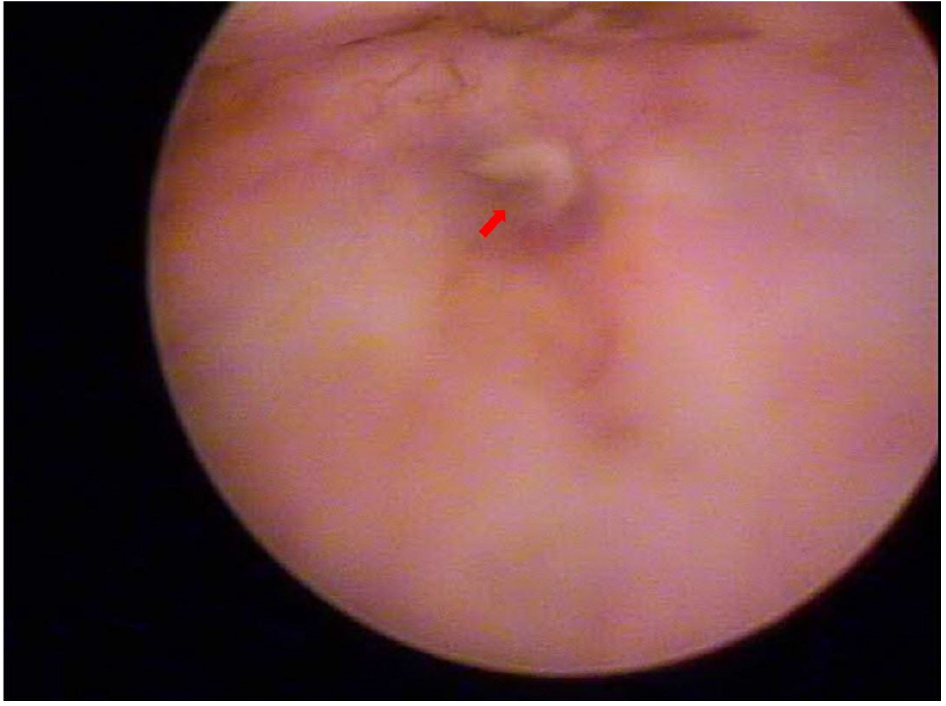

35세 여성이 몇 달 전부터 배꼽에서 소변이 나오는 것을 주 증상으로 내원하였다. 수년 전부터 시작되었다고는 하나 그때는 분비량이 매우 적어 별다른 신경을 쓰지 않고 살아왔으며, 최근 들어서 그 양이 점점 증가하였다고 하였다. 특히 성관계 시에 나오는 양이 상당히 많았으며, 소변을 참거나 배에 힘을 주면 증가한다고 하였다. 배꼽으로 소변이 나오는 것 외에 육안적 혈뇨나 배뇨통 등은동반되지 않았다고 하였다. 미혼 여성으로 출산력은 없었으며 그 밖에 과거력 상 특이사항은 없었다. 신체검사에서 배꼽은 정상적인 모양을 하고 있었으나, 방광경 검사에서 방광 전벽에 개구부가 확인되었으며 [그림 1], 양측 요관구는 정상적인 위치에 있었고, 방광내의 종물 등은 관찰되지 않았다. 내원하여 시행한 요배양 검사에서는 Streptococcus anginosus가 배양되었으며, 요세포 검사에서 이상은 발견되지 않았다. 이후 촬영한 복부 전산화 단층촬영에서 배꼽에서 방광 전벽까지 연결되는 튜브 모양의 구조물이 관찰되어 개방 요막관으로 진단하였으며 [그림 2], 주변으로 석회화나 이상 종괴는 발견되지 않았다. 항생제 경구 복용을 시작하였으며, 수술적인 치료가 계획되었다.